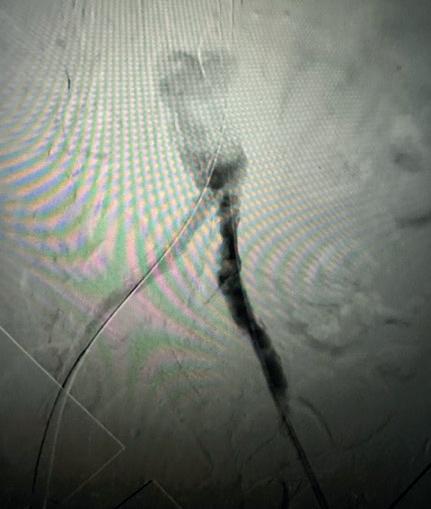

Case 2: The Shockwave M5+ tackles 90% stenosis of the distal SFA

The patient is a 75-year-old man with a history of hypertension, hyperlipidemia, CAD, chronic kidney disease and diabetes mellitus, who presents with a non-healing wound of the right lower extremity for three months. He had undergone diagnostic work—his ankle-brachial index (ABI) was found to be 0.73 with a toe pressure of 50mmhg, and a duplex ultrasound revealed a densely calcified superficial femoral artery (SFA) stenosis of 90%.

He was taken to the cath lab and underwent a right lower-extremity arteriogram. This confirmed a 90% stenosis of the distal SFA, with normal three-vessel run off. Due to the heavy calcium, we opted for a Shockwave M5+ 6x60mm and delivered 200 pulses to the lesion. There was no appreciable residual stenosis at the completion of the procedure, and his post-procedure ABI improved to 1.

This is a great example of how IVL can be used as a standalone therapy without the need for adjunctive treatment.

Figure 1. Pre-procedural angiogram

Figure 2. Pre-procedural angiogram

Figure 5. Final angiogram

Figure 2. IVL treatment angiogram

Figure 3. Post-IVL angiogram